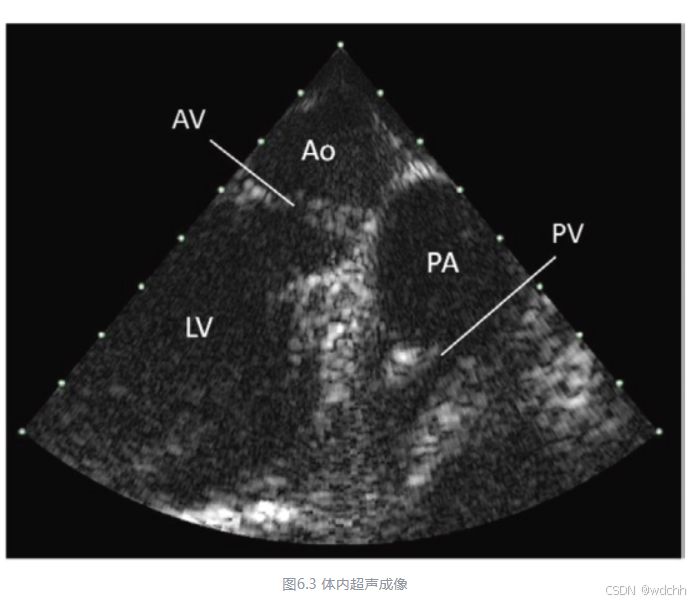

6.3血管内超声成像

血管内超声成像(IVUS)为心血管疾病的诊断搭了一条新路,该技术搭载超声探头和微电机,钻进血管内部,成像出血管侧壁的图像,对于因钙化、纤维化等造成的血栓等病变进行诊断。

由于是血管内成像,体积是IVUS的最大限制,因此微机械超声换能器是当前唯一的选择。IVUS有机械旋转成像和相控阵成像,其原理和区别也和类似于扫描式和静态式成像。它们的核心都在于体积小,振元密度大,这是只有PMUT才能完成的任务。

当然,客观地说,相比于汽车和消费电子,医疗领域的产品,技术换代相对缓一些,由于需要安全第一,医疗厂商往往并不会追寻最新的技术应用到当下的产品中。因此,PMUT在医疗领域的应用,可能会迟缓一些,目前来说还不是成熟的商业化推广领域。